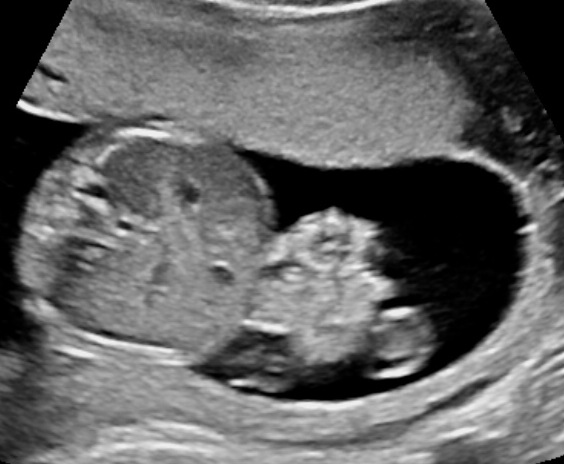

Appearance

The characteristic ultrasound appearance of gastroschisis is that of cauliflower‐like intestinal loops floating in the amniotic fluid.4